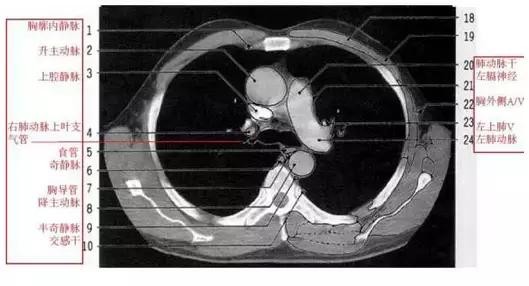

详尽的胸部CT影像示意图

胸部的CT是通过X线计算机体层摄影(CT)对胸部进行检查的一种方法。正常胸部CT层面较多,每一层面结构所表现的图像不同。下面是胸部CT图文示意图,可帮助临床医生详细了解CT结构。我们一起来看一下吧。

来源:影像论坛